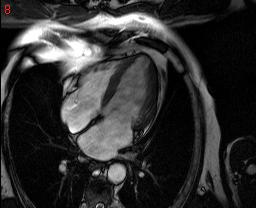

cardiac mri is some thing which can save many lives but the software available to analyse them are too costly...

the pictures show a few cardiac MRI data.. is there any way we can crop out hust the heart ,

itried a few thresholding scheles but, they dont seem to work very well